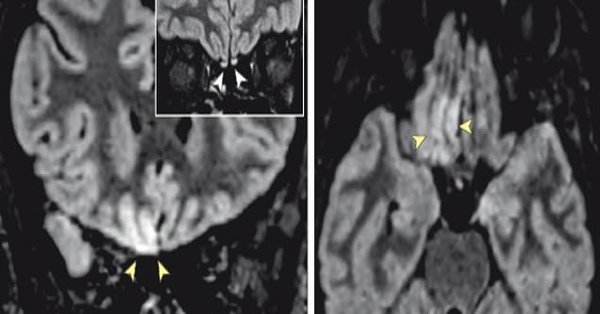

وتظهر الصور تقلبات طفيفة في منطقة من الدماغ تتحكم في حاسة الشم لدينا.

ووجدوا تغيرات في دماغها في منطقتين: منطقة تسمى التلفيف المستقيم الأيمن ومنطقة تسمى البصلات الشمية.

وتأخذ البصلات الشمية معلومات حسية من الأنف وتمررها إلى مناطق أخرى، بما في ذلك التلفيف المستقيم، للمعالجة.

وكانت الطريقة التي ظهرت بها هذه التغييرات في التصوير بالرنين المغناطيسي متسقة مع نوع الصور التي يتوقع الأطباء رؤيتها من الهجمات الفيروسية على العضو، لذلك قاموا باختبار المرأة للتحقق من وجود فيروس كورونا. وكان اختبارها إيجابيا.

وبعد 28 يوما، قام الأطباء بإجراء تصوير بالرنين المغناطيسي مرة أخرى، ورأوا أن دماغها بدأ في العودة إلى طبيعته، على الرغم من أن البصلات الشمية ظلت ملتهبة قليلا.

وكتب مؤلفو الدراسة: "بناء على نتائج التصوير بالرنين المغناطيسي، بما في ذلك التغيرات الطفيفة في البصلة الشمية، يمكننا التكهن بأن SARS-CoV-2 قد يغزو الدماغ من خلال مسار حاسة الشم ويسبب خللا في حاسة الشم".